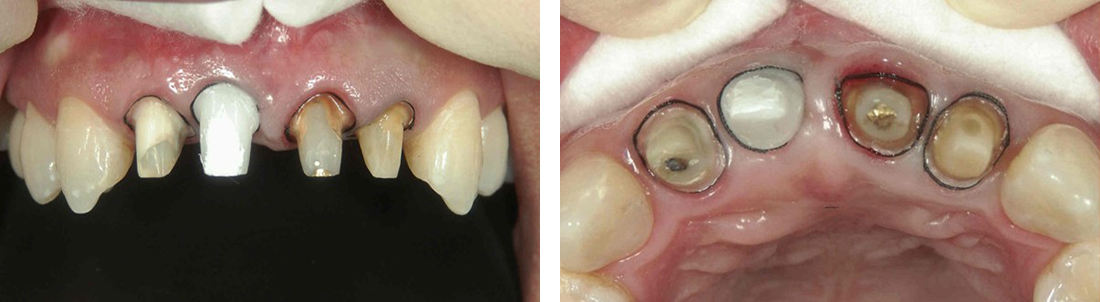

インプラント症例 Case3

Treatment cases

Before

After